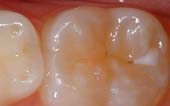

Seal Out Decay

A sealant is a protective coating that is applied to the chewing surfaces (grooves) of the back teeth (premolars and molars), where four out of five cavities in children are found. This sealant acts as a barrier to food, plaque and acid, thus protecting the decay-prone areas of the teeth.

Before Sealant Applied

After Sealant Applied